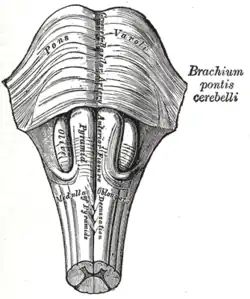

La face antérieure de la moelle allongée est parcourue parasagittalement par deux sillons ventraux de part et d'autre du sillon ventro-médian, lesquels s'évasent dans la partie supérieure (rostrale) pour enserrer à droite et à gauche deux reliefs hémisphériques : les olives bulbaires.